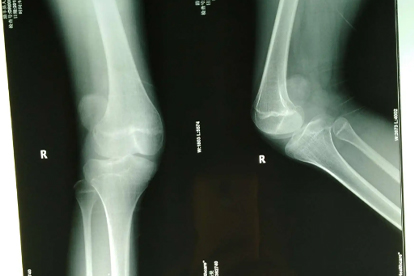

髌骨脱位如何消肿 髌骨脱位3消肿方法揭秘

髌骨脱位可通过冰敷、加压包扎、抬高患肢等方式消肿。髌骨脱位通常由外伤、先天发育异常、肌肉力量失衡等原因引起。